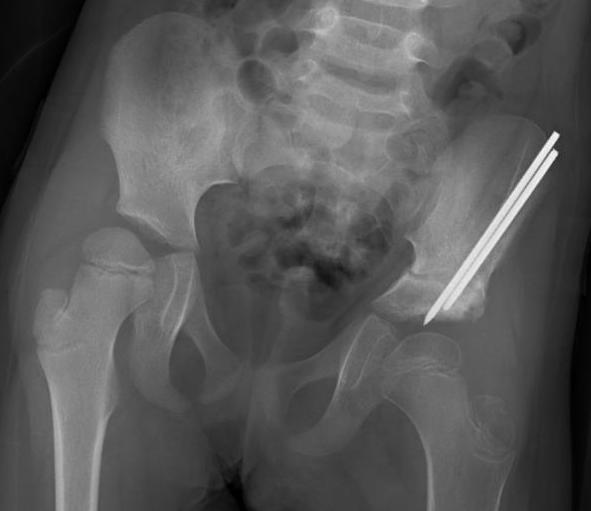

Xray

Dislocated hips in the setting of DDH with ncreased acetabular index